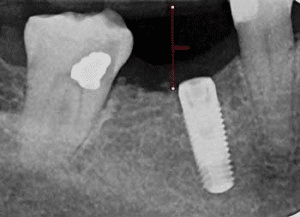

See the following examples of implants placed in the lower right first molar in two different patients.

Patient Experience: Case 2

Implant Placed without Using a Surgical Guide

Notice the difference in positioning between the guided placement and the freehand placement. The ideally placed implant in Case 1 is centered in the available bone space, allowing for optimal restoration design and long-term stability. This is the standard of care that Dr. Marlin follows for every implant placement.